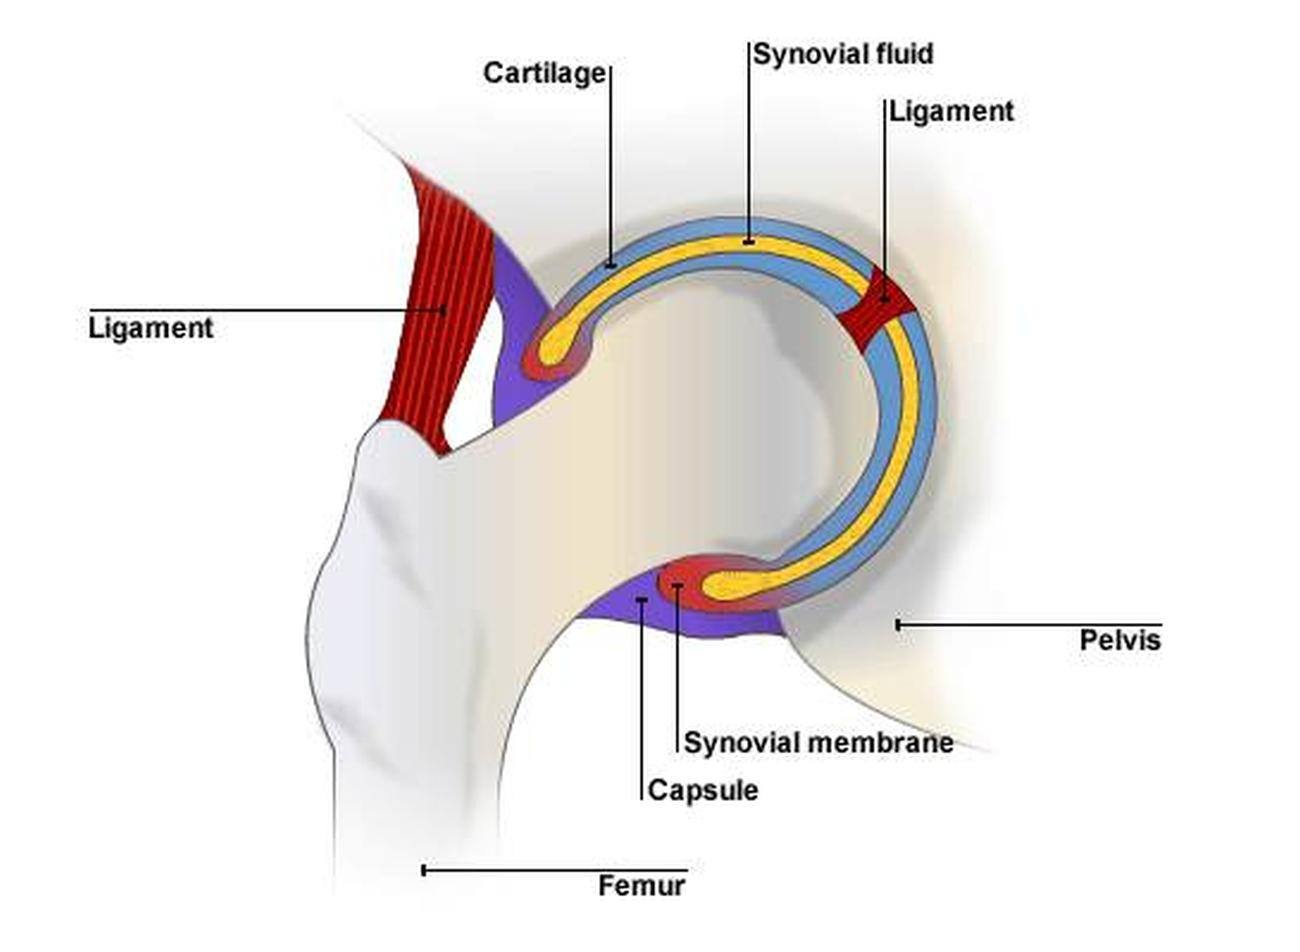

Рентгеновские снимки: Синовит тазобедренного сустава